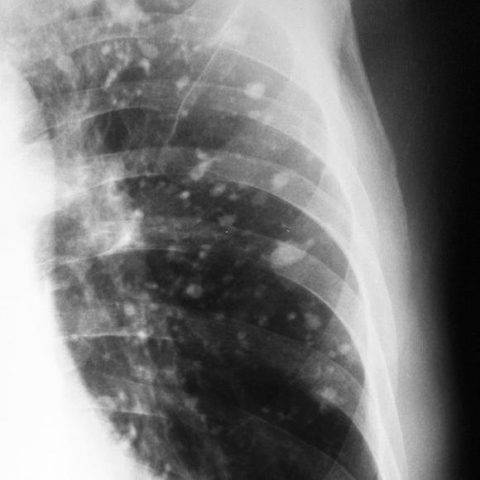

Характерными признаками действия вируса будут изменения легочных полей в виде очагов (от одиночного до диффузных). Вирусная пневмония выглядит на томографии легких как совокупность типичных изменений.

- «Матовое стекло» — очаг просветления легочного поля из-за снижения воздушности в сочетании воспаления и утолщения межальвеолярных перегородок, заполнения альвеол жидкостью.

- Очаги округлые, могут сливаться между собой и распространяться на большую часть легочного поля. Чаще располагаются на периферии ближе к плевре. Чаще в нижних сегментах.

- «Булыжная мостовая» — утолщение пространства между легочными дольками, за счет чего они выглядят, как разрозненные части дороги.

- Консолидация — уплотнение легочной ткани за счет заполнения альвеол жидкостью.

- Симптом обратного ореола — кольцо консолидации вокруг участка “матового стекла”

- «Воздушная бронхограмма» — просвет бронха, пересекающего участок уплотнения легкого.

- Отмечается чаще двустороннее поражение.

- В отличие от бактериальной пневмонии реже наблюдается усиление легочного рисунка.